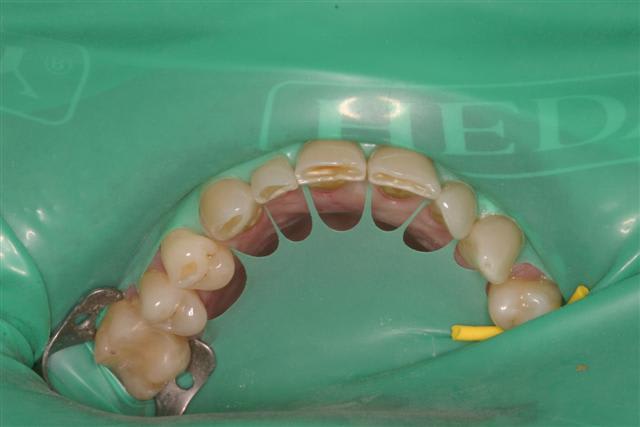

Même et surtout pour les cas complexes (essai et cimentation de 6 à 10 unités céramique)la digue est un outil très utile. Je peux etcher, placer l'adhésif, prendre mon temps pour coller sans avoir la langue, la salive etc.